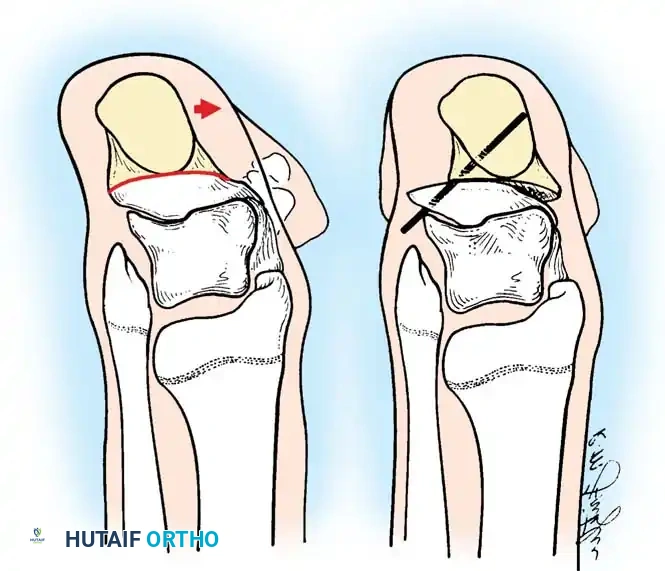

تشوهات القدم في الشلل الدماغي هي حالة شائعة ناتجة عن التشنج العضلي المستمر، وأبرزها القدم الخيلية أو المشي على أطراف الأصابع. يبدأ العلاج بالطرق التحفظية مثل الجبائر وحقن البوتكس، وقد يتطلب تدخلاً جراحياً دقيقاً لتطويل الأوتار وتصحيح العظام لضمان قدرة الطفل على المشي بشكل طبيعي ومستقل.

الخلاصة الطبية السريعة: تشوهات القدم في الشلل الدماغي هي حالة شائعة ناتجة عن التشنج العضلي المستمر، وأبرزها القدم الخيلية أو المشي على أطراف الأصابع. يبدأ العلاج بالطرق التحفظية مثل الجبائر وحقن البوتكس، وقد يتطلب تدخلاً جراحياً دقيقاً لتطويل الأوتار وتصحيح العظام لضمان قدرة الطفل على المشي بشكل طبيعي ومستقل.